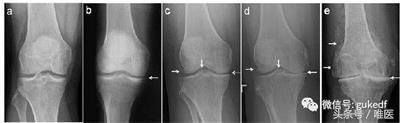

经常会遇到有人发现自己“关节疼、肿”,到医院拍片,诊断为“滑膜炎”(图1a,1b)、“骨质增生”(图1c,1d,1e),还有诊断为“关节炎”的(图1d,1e)。那到底是哪种病?我们对这几种病名分别了解一下。

图1.膝关节的各种X线拍片表现

从上可见,关节软骨磨损、骨关节炎就会继发滑膜炎。因为在常规X线片上无法观察到明显的关节周围骨质增生(骨赘、骨刺形成),或关节间隙变窄(图1c,1d,1e),因此被称之为“滑膜炎”。

患者关节肿痛,拍片子后看到报告单上描述的“骨质增生”,同时观察到X线片上关节(股骨或胫骨)周缘或髁间棘处增生的骨质(图1c,1d,1e左侧和中间白箭头),就断定自己得了“骨质增生”(有了“骨刺”)。

从前面我们可以知道,过度活动或年龄增大会导致关节磨损。轻度的关节损伤会导致“滑膜炎”;重度的关节损伤或年龄增大导致关节磨损会导致“退行性骨关节炎”,也就是常说的“关节炎”(图1c,1d,1e)。